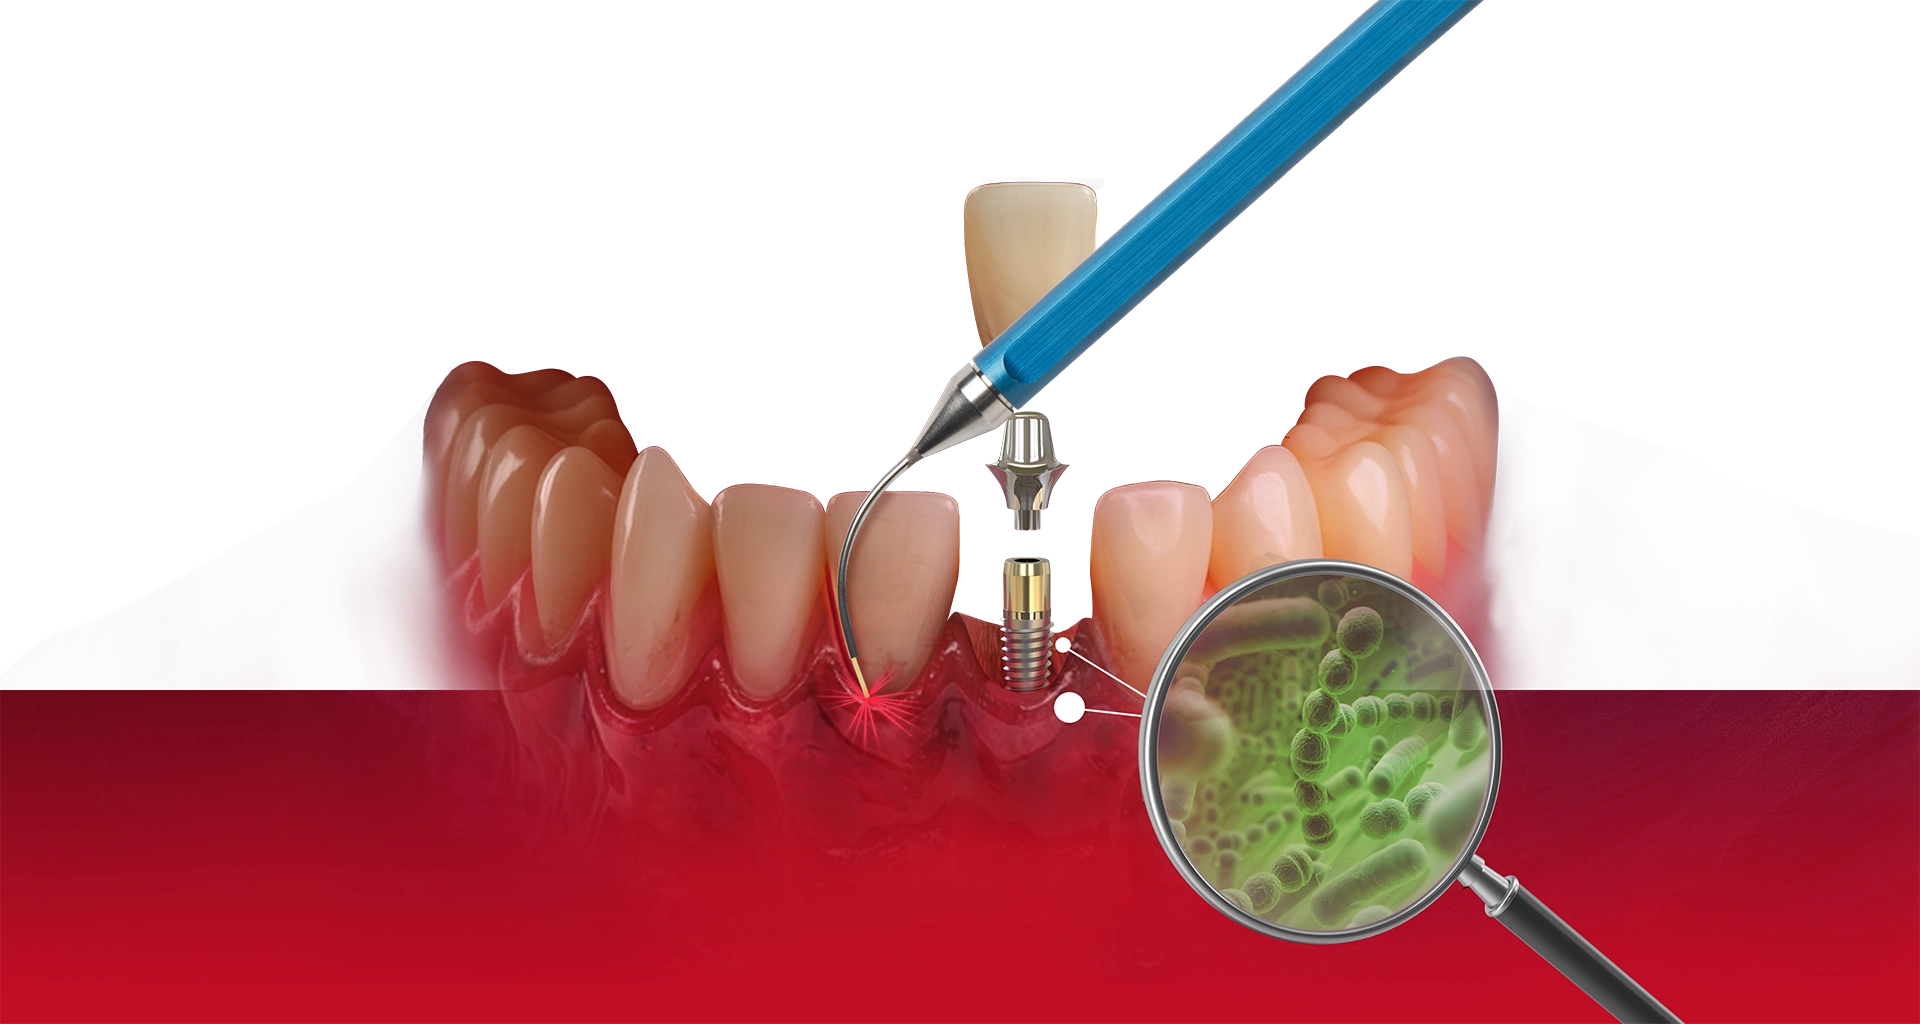

The LAPIP protocol offers a minimally invasive, laser-based method for treating peri-implantitis—the inflammation and bone loss that threatens the stability of dental implants. Using the same PerioLase® MVP-7™ technology as LANAP, LAPIP precisely targets infected tissue and harmful bacteria surrounding the implant while protecting healthy gum and bone. This allows the body to naturally rebuild lost support and helps save implants that would otherwise be at risk of failure. With no cutting or sutures required, LAPIP provides a gentle, highly effective alternative to traditional peri-implant surgery.

LAPIP™ (Laser-Assisted Peri-Implant Procedure) is a minimally invasive laser treatment designed to save ailing or failing dental implants caused by peri-implantitis. Using the PerioLase® MVP-7™ Nd:YAG laser, the protocol targets inflamed, infected tissue and titanium corrosion contaminants while preserving healthy gums and bone. This tissue-sparing approach promotes bone regeneration around the implant and offers a more comfortable treatment with less bleeding, swelling, and downtime than traditional surgery.

Traditional gum and implant surgery often requires cutting into the tissue, lifting flaps, and stitching the area closed afterward. These methods can increase trauma, bleeding, swelling, and longer recovery times. LANAP and LAPIP eliminate the need for scalpels or sutures by using the PerioLase® MVP-7™ laser to selectively remove infection while protecting healthy gum and bone—whether around natural teeth or dental implants.

Both LANAP and LAPIP use laser energy that targets only infected tissue and harmful bacteria. Unlike scalpels, the PerioLase® MVP-7™ does not cut healthy gum or bone, meaning less inflammation, less bleeding, and less postoperative discomfort. This precision also allows for regeneration of the supporting structures—whether around natural teeth (LANAP) or implants (LAPIP)—helping stabilize areas affected by disease.